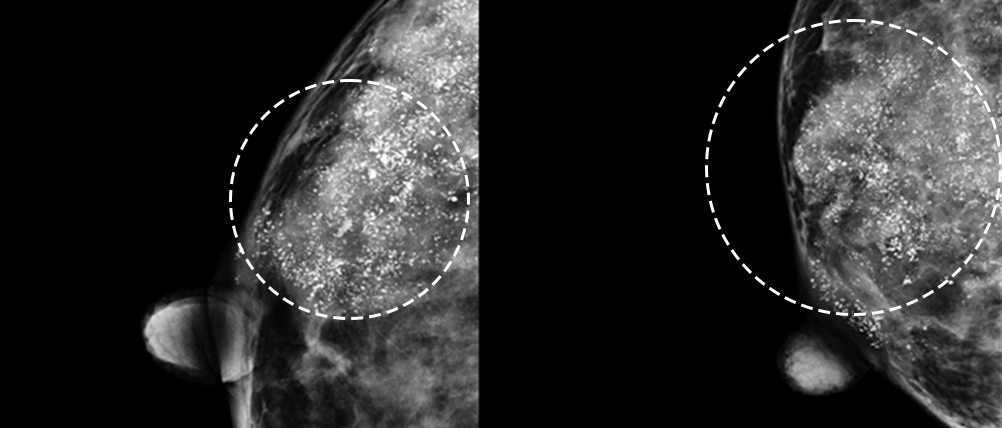

미세석회화 -

군집성 미세석회화

* 미세석회화: 0.5mm 이하로 작고 단위면적당 입자수가 많으며 크기와 모양이 균일하지 않음

* 군집성 미세석회화: 단위면적당 5~10개 이상 모여 있는 경우

※ 양성석회라도 모양, 수 등 양상의 변화가 있는 경우 주의를 기울여야 합니다.